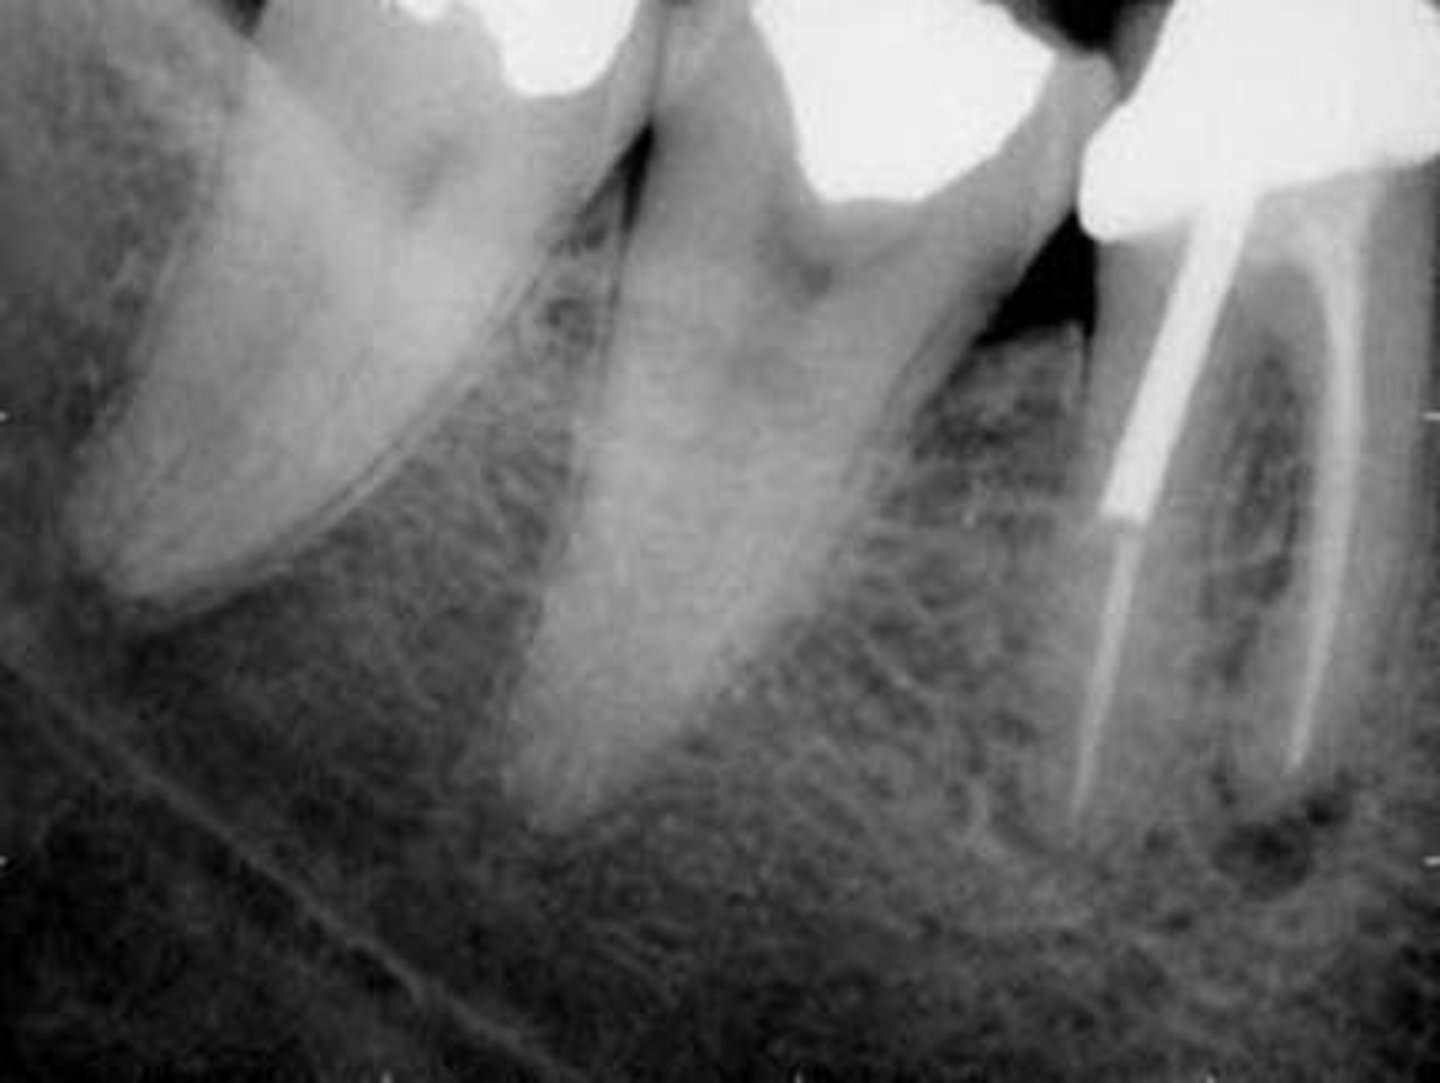

elongation

foreshortening